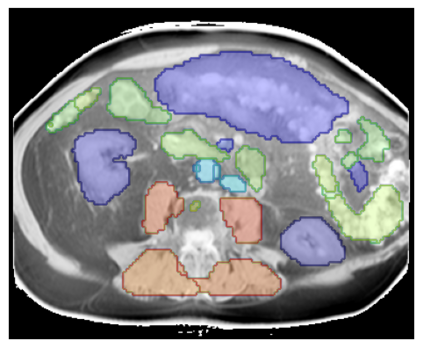

Purpose: To introduce a deep learning model capable of multi-organ segmentation in MRI scans, offering a solution to the current limitations in MRI analysis due to challenges in resolution, standardized intensity values, and variability in sequences. Materials and Methods: he model was trained on 1,200 manually annotated MRI scans from the UK Biobank, 221 in-house MRI scans and 1228 CT scans, leveraging cross-modality transfer learning from CT segmentation models. A human-in-the-loop annotation workflow was employed to efficiently create high-quality segmentations. The model's performance was evaluated on NAKO and the AMOS22 dataset containing 600 and 60 MRI examinations. Dice Similarity Coefficient (DSC) and Hausdorff Distance (HD) was used to assess segmentation accuracy. The model will be open sourced. Results: The model showcased high accuracy in segmenting well-defined organs, achieving Dice Similarity Coefficient (DSC) scores of 0.97 for the right and left lungs, and 0.95 for the heart. It also demonstrated robustness in organs like the liver (DSC: 0.96) and kidneys (DSC: 0.95 left, 0.95 right), which present more variability. However, segmentation of smaller and complex structures such as the portal and splenic veins (DSC: 0.54) and adrenal glands (DSC: 0.65 left, 0.61 right) revealed the need for further model optimization. Conclusion: The proposed model is a robust, tool for accurate segmentation of 40 anatomical structures in MRI and CT images. By leveraging cross-modality learning and interactive annotation, the model achieves strong performance and generalizability across diverse datasets, making it a valuable resource for researchers and clinicians. It is open source and can be downloaded from https://github.com/hhaentze/MRSegmentator.